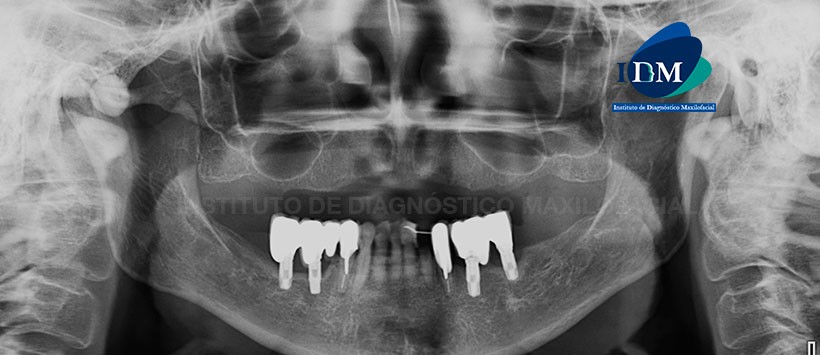

Paciente de 70 años acude al Instituto de Diagnóstico Maxilofacial para evaluación imagenológica indicada para la colocación de implantes.

A la evaluación de la radiografía panorámica se aprecia la neumatizacion alveolar de ambos senos maxilares, reabsorción osea alveolar moderada bimaxilar, ausencia de múltiples piezas dentarias, presencia de implantes y protesis sobre implantes en sector mandibular posterior, piezas 33 y 44 presentan material de obturación con espigos y coronas protésicas. Sin embargo lo mas resaltane es la imagen radiopaca de forma redondeada, de limites definidos y proyectada sobre el arco cigomático de lado derecho. (Figura 1)